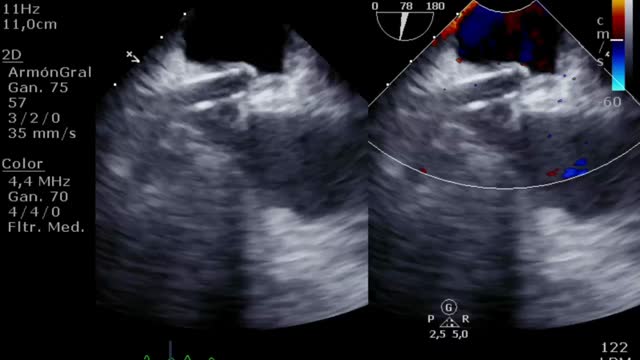

Por último, muchos de los pacientes con ECMO VA pueden tener algún otro dispositivo de asistencia ventricular izquierda (BCIAo, Impella®) como medida de descarga ventricular34 y de los que también deberemos controlar su posición y funcionamiento12. En el caso del BCIAo, mediante ETT/ETE podremos observar el inflado del balón a nivel de la aorta descendente con su extremo distal a nivel del nacimiento de la subclavia izquierda (suplementario 17). El Impella® se puede explorar tanto por ETT (paraesternal de eje largo o apical de 3 cámaras) como por ETE (mediesofágico 120°) y debemos observar el dispositivo entrando desde la aorta ascendente y el inlet o zona de succión a 3-4cm de la válvula aórtica35,36 (fig. 4 y suplementario 18).